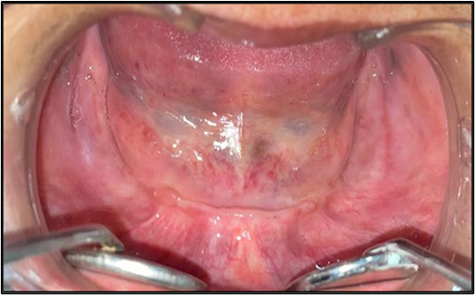

Figure 2: Resorbed Mandibular Ridge.

A 58-year-old female, presented with complaint of constant dislodgement of her denture during chewing, accompanied by significant difficulty in chewing food over the past eight months. Her dental history showed a gradual loss of teeth spanning approximately seven years, with complete edentulism established six years ago. A pre-treatment panoramic radiograph revealed generalized alveolar bone resorption, more pronounced in the mandibular ridge. The maxillary alveolar ridge exhibited moderate resorption, with diminished bone height particularly in the anterior region corresponding to the flabby premaxillary tissue. A conservative, non-surgical prosthodontic rehabilitation was planned.

The rehabilitation of completely edentulous patients remains a clinical challenge, particularly in the presence of compromised ridge condition such as flabby tissues. According to Glossary of Prosthodontic Terms (GPT) 9-Flabby tissue is defined as excessive, movable tissue. Flabby tissue or hypermobile ridge tissue is commonly seen in the anterior part of the edentulous maxillary ridge or an atrophic knife-edge mandibular ridge which adversely affect the support, stability and retention of conventional dentures. It is commonly associated with long-term denture wear, traumatic occlusion or residual ridge resorption. Successful management requires accurate impression techniques that record the flabby tissues without distortion, thereby ensuring optimal prosthesis function and patient comfort.